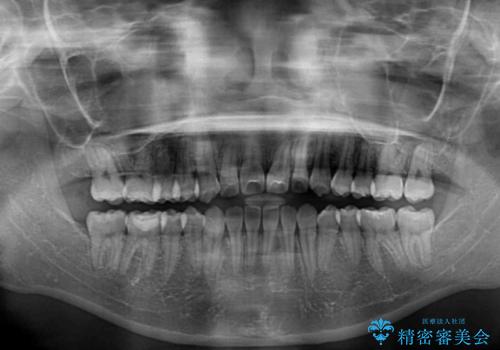

- メタルブラケット

- 1年2ヶ月

- 10-30回